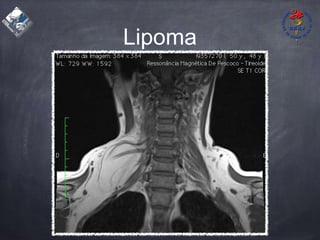

Lipoma